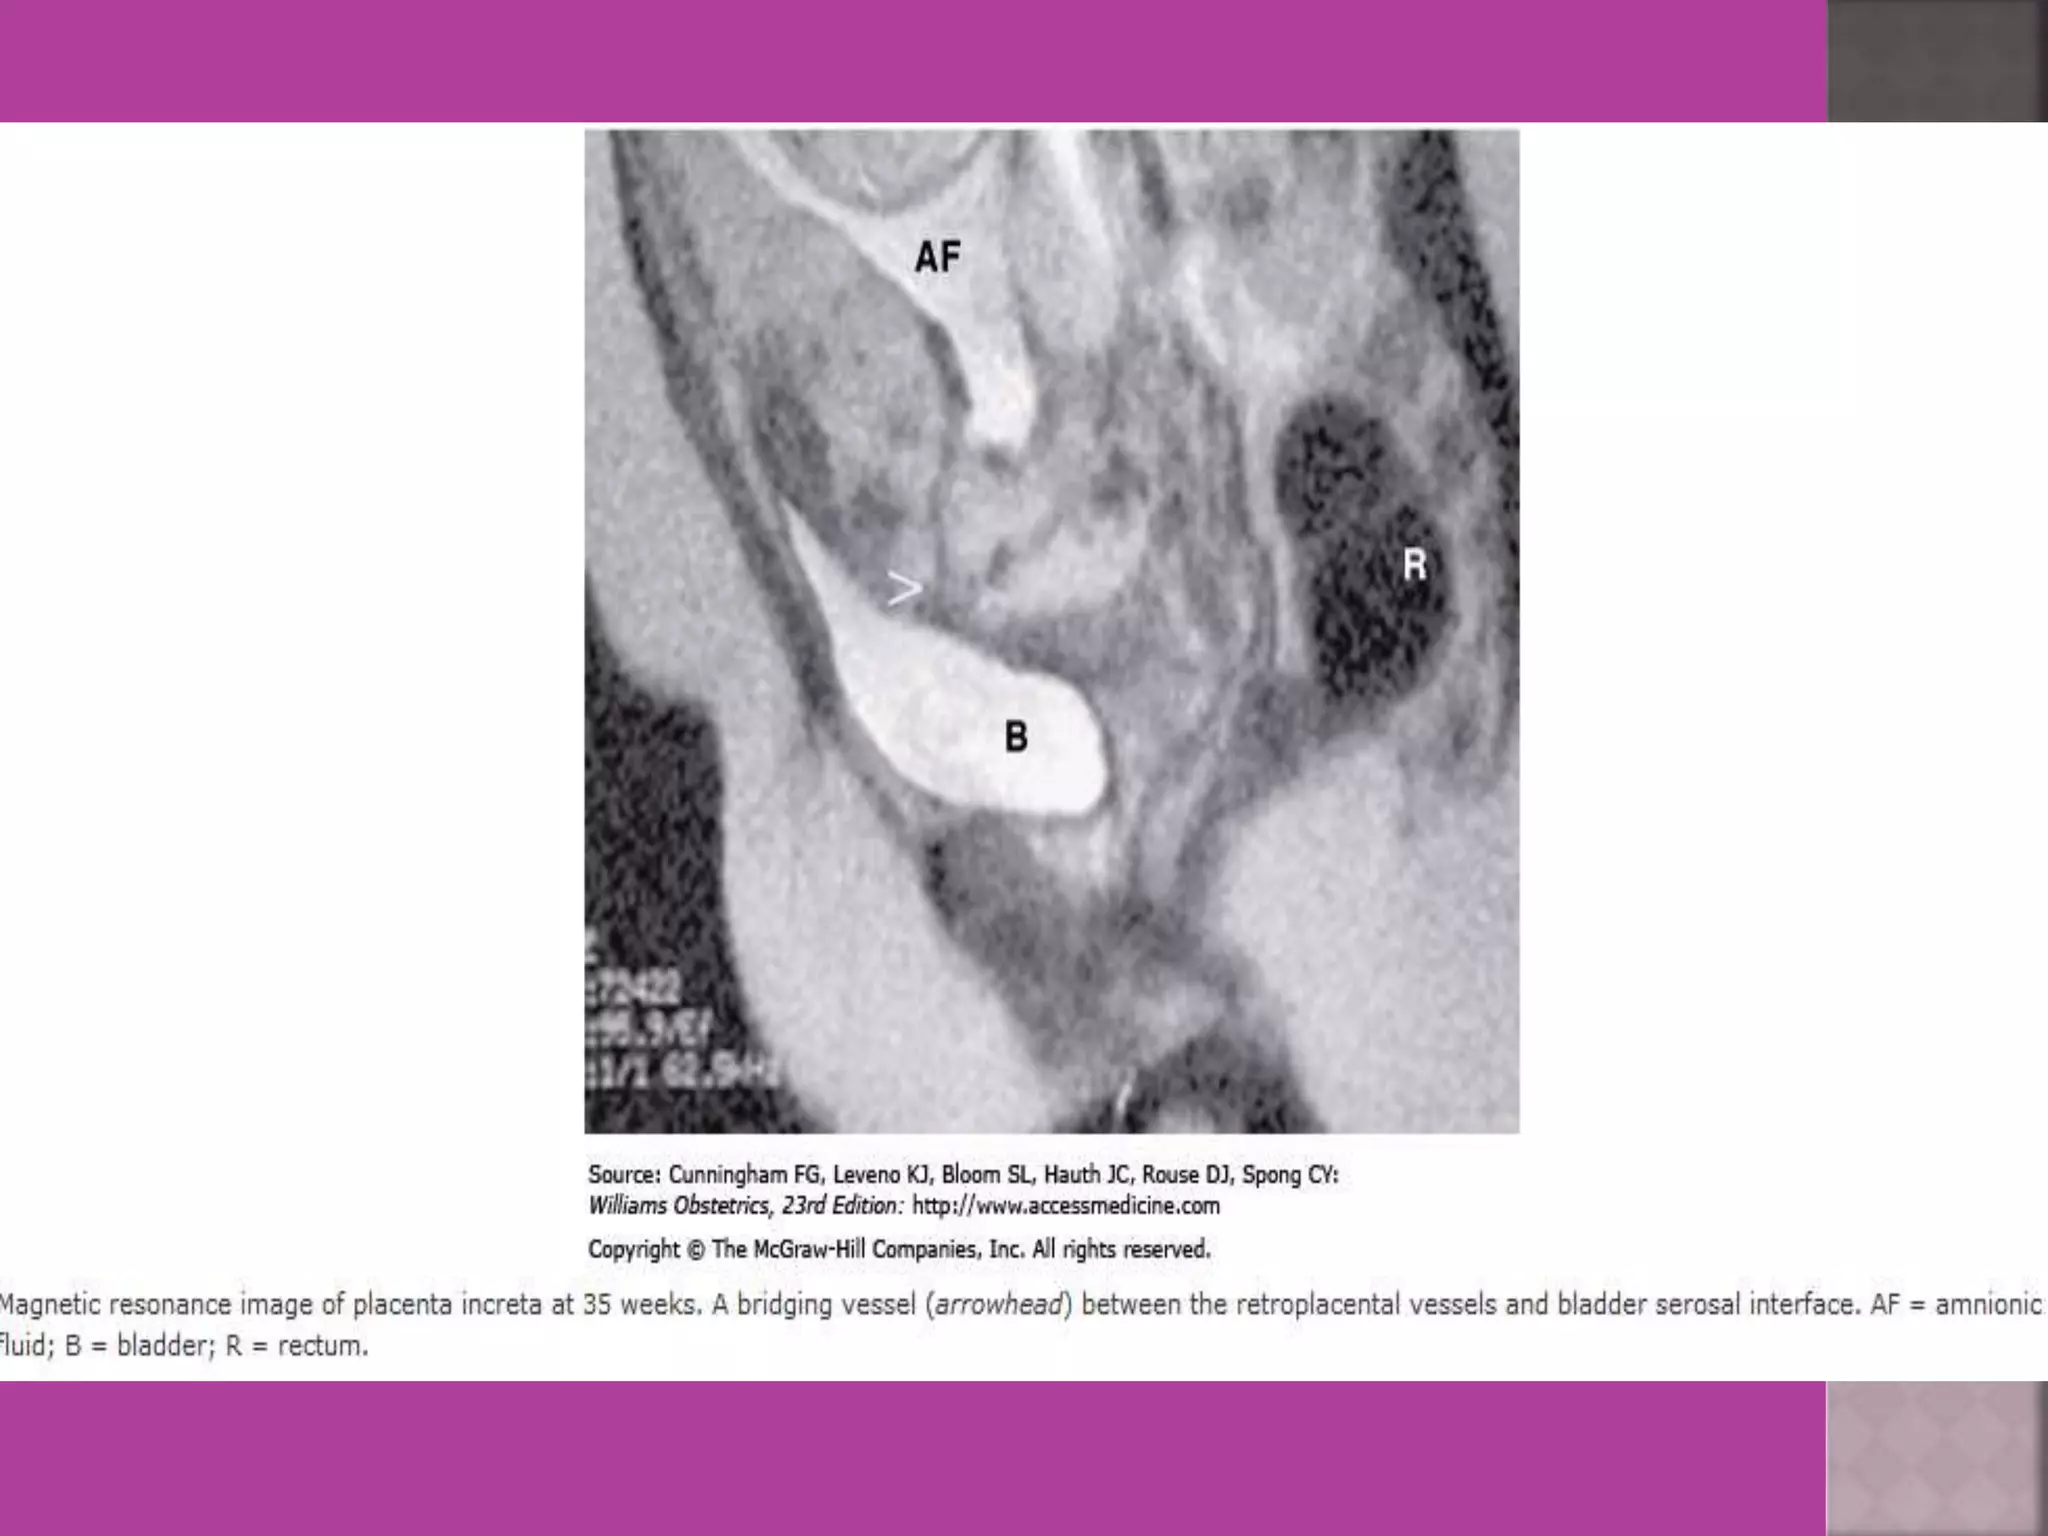

4. Pregnancy --- complicated by genital

cancers

 As it is safe in pregnancy –it is useful in diagnosis of

obstetrical conditions as well s differentiation of

tumors (benign / malignant ) complicating pregnancy.

 MRI ismost sensitive for diagnosis of Adenomyosis.  MRI Is more accurate and informative in diagnosis of congenital malformation of genito-urinary tract.  Retroparitoneal lymph node > 1cm can be identified so also such small deposits on bowel / bladder liver can be identified in cases of cancers.  It is more sensitive and accurate tool to assess infiltration of myometrial/ cervical wall, adjoining organs and parametrium --thus helps in pre operative staging of genital carcinomas.  As it is safe in pregnancy –it is useful in diagnosis of obstetrical conditions as well s differentiation of tumors (benign / malignant ) complicating pregnancy.